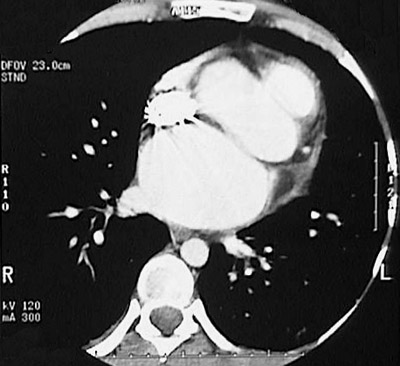

This chest CT scan demonstrates marked left atrial enlargement in a patient with mitral valve disease that required replacement with a prosthetic mitral valve.